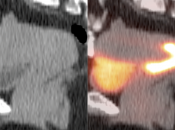

- Liver Ablation